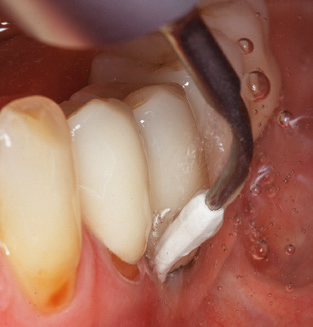

Of course, working tips for the cleaning of implant surfaces are also indispensable for SPT in patients fitted with implants. The implant cleaning attachment on the system used here is characterised by its tapered, hexagonal design. This design allows light, atraumatic penetration of the peri-implant pocket and displays a good cleaning performance (Fig. 7).

Following machine cleaning of the tooth and implant surfaces, the surfaces of the natural teeth are cleaned manually using standard hand instruments. When performing manual cleaning, particular attention must be given to maintaining the correct angle of application, appropriate sharpness, good support and working with the curette from apical to coronal. Either titanium or carbon curettes should be used for post-cleaning of the implant structures (Fig. 8). In addition to the use of ultrasonic devices, power jet devices can also be used in conservative dentistry. However, it must be taken into consideration that these procedures are not suitable for removing hard deposits and thus they cannot replace the use of hand instruments and ultrasonic instruments completely. In all cases, cleaning is followed by mechanical polishing of the accessible tooth and implant surfaces with polishing cups and polishing compounds (Fig. 9).

Fig. 4: Flexible probes with millimetre markings are recommended for the probing of dental implants (e.g. Colorvue Kit PCV11KIT6, Hu­Friedy). – Fig. 5a and b: A straight working tip (1P, W&H Dentalwerk Bürmoos GmbH) is a suitable instrument for use on all natural teeth. – Fig. 6: Curved working tips (3Pr/3Pl, W&H Dentalwerk Bürmoos GmbH) lend themselves to the processing of difficult-to-reach areas of the tooth and root surfaces (e.g. furcations). – Fig. 7: The tapered, hexagonal implant cleaning tip (1I, W&H Dentalwerk Bürmoos GmbH) permits atraumatic and efficient cleaning of the crown and abutment surfaces. – Fig. 8: Titanium and carbon curettes are suitable instruments for the manual cleaning of the implant surfaces.